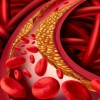

![]() Thiếu máu não là tình trạng máu lưu thông lên não kém dẫn đến không cung cấp đủ dinh dưỡng và oxy cần thiết cho các hoạt động của não

Thiếu máu não là tình trạng máu lưu thông lên não kém dẫn đến không cung cấp đủ dinh dưỡng và oxy cần thiết cho các hoạt động của não

![]() Dấu hiệu: Đau đầu, hoa mắt, chóng mặt, mất ngủ...

Dấu hiệu: Đau đầu, hoa mắt, chóng mặt, mất ngủ...

Chế độ ăn uống nhiều chất béo bão hòa, hàm lượng muối cao và nhiều chất bảo quản chính là “kẻ thù” của người bị thiếu máu não: